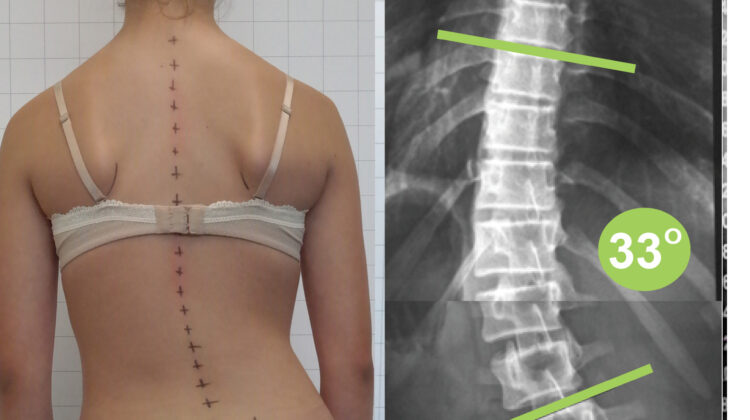

الحقيقة الرابعة: حزام اعوجاج العمود الفقري مثل PioBrace لا يوقف التدهور فقط… بل يحسن الانحناء

✔️ الحقيقة: في بعض الحالات، يساعد في تحسين درجة الانحناء

متى يكون الحزام فعالًا؟

- عند اكتشاف الحالة مبكرًا

- عندما يكون الطفل ما زال ينمو

- مع الالتزام بعدد ساعات الارتداء